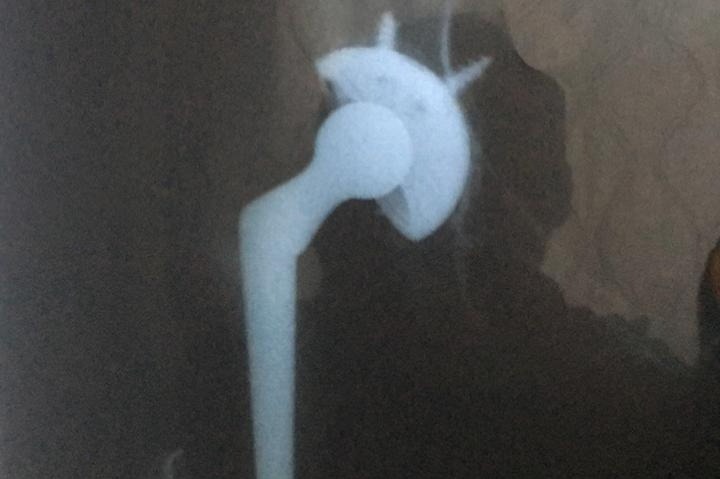

To all my family, friends, friend of friends, colleagues and everyone that can help, this is my friend Gloria. We have known each other for about 10 years now and she resides in El Salvador. She is struggling with medical care expenses, due to COVID-19 restrictions causing her business to shutdown for several months. She moved into our house in Santa Tecla, because she could not continue to pay her own house until she got back on her feet, but now she is faced with another hip surgery, due to a fall earlier in the year when she broke her other hip. Gloria is a very proud person and it took a lot of begging her to allow me to do this for her, because has always been the provider in her family. She is seeing her long time customers and trying to retain her cliental even when she is on crutches and in extreme pain. Her hip surgery, physical therapy and medication costs is going to run over $10k.